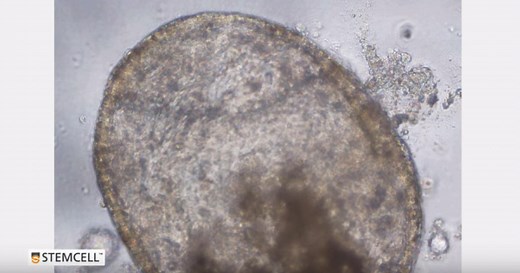

Lung Organoid Testing 的热门建议 |